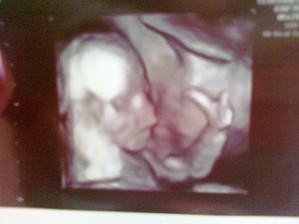

29.7.2011 - USG vyšetrenie. Všetko je v úplnom poriadku. Bábätká zodpovedajú veku 19+3 tt., termín pôrodu 20.12.2011. Čakáme chlapčeka a dievčatko, jedno má 298 g a druhé 290 g.

12.10.2011 - poradňa, zase všetko v najlepšom poriadku. USG dopadol výborne, dievčatko dole hlavičkou, váhu má 1700 g a chlapček hore hlavičkou, váhu má 1600 g. Povedal, že majú krásne váhy v 30 + 1 tt. Ak sa nič nepredvídané nestane, budeme rodiť prirodzene. Zatiaľ som pribrala 3 kg od pôvodnej váhy, resp. 5,5 kg od schudnutej váhy...🙂. Ďalšia poradňa 28.10.2011 + objednávka na prietoky.

7.11.2011 - prietoky v poriadku, jedno 0,63 a druhé 0,64. Chlapček sa nám konečne umúdril a otočil sa dole hlavičkou. A odhadované váhy v 33+6 tt. mal chlapec 2340 g a dievčatko 2320 g. Povedal, že sú krásne rovnomerne veľké, dokonca väčšie na ten týždeň tehotenstva. Poradňa 10.11.2011.